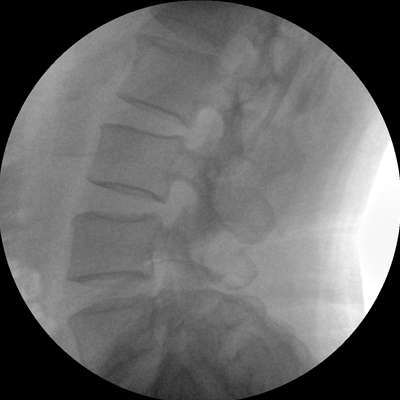

Clinical picture

臨床圖片